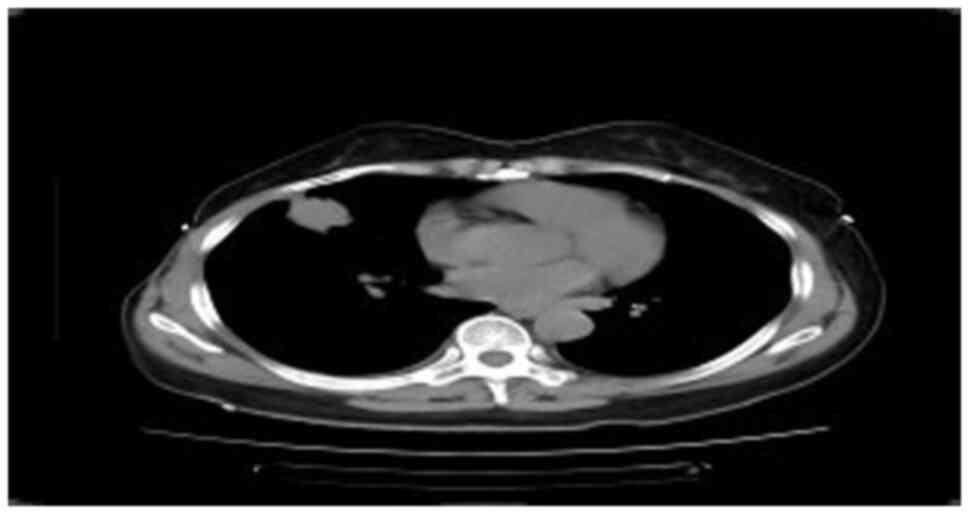

Chest CT (Fig. 1) revealed a mass in the middle lobe of the right lung, measuring ~3.1×2.8×2.8 cm in size, with small burrs and traction near the pleura. Multiple small nodules were observed in the right lung, and the diameter of the largest nodule was ~1.0 cm; no abnormalities of the cardiac shadow, mediastinum and bilateral hilum were observed. There was a small effusion in the right thoracic cavity along with local pleural thickening on the right side. In January 2023, ultrasound bronchoscopic biopsy was performed on the outer segment of the right middle lung. Positron emission tomography-CT examination, also carried out in January 2023, revealed a mass in the lateral segment of the right middle lobe of the lung, measuring ~3.5×2.5×2.5 cm in size, which was clear with no uniform boundary, and showed roughly uniform internal density, increased uptake of fluorodeoxyglucose (FDG), distal bronchus truncation in the lateral segment of the right middle lobe, and unclear boundary between the lesion and the adjacent pleura. A few fibrous cord shadows could be observed in the upper lobe of the lingual and base segments of the lower lobe of the left lung. No abnormal density lesions, such as nodules and masses, were observed in the remaining two lung fields, and no abnormal FDG metabolism was observed. Nodular thickening and increased FDG uptake were observed in the right pleura, including the lateral, interlobular fissure and diaphragmatic pleura. A small effusion in the right thoracic cavity was visible. Slightly larger lymph nodes were found in the right hilum of the lung and mediastinum behind the anterior tracheal vena cava and under the carina. The larger lymph nodes were located behind the anterior tracheal vena cava, with a diameterof~1.8cm and increased uptake of FDG.

Figure 1.

Chest computed tomography revealed a mass in the middle lobe of the right lung with small burrs and traction near the pleura.